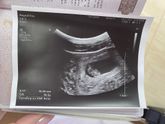

Завтра иду на первый скрининг, хочу скорее увидеть моего зайчика ? и услышать , что все хорошо !